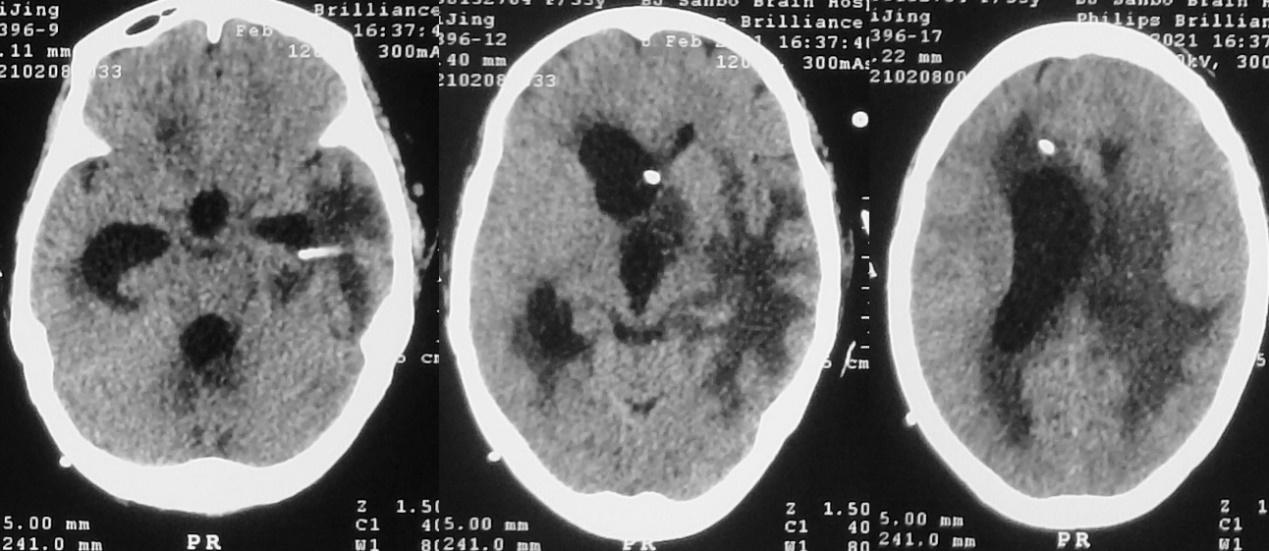

患者于2020年11月8日无明显诱因出现间断头痛。发病5天后,即2020年11月13日到当地的河南省潢川县某医院行头颅CT检查( 图-1 )发现左侧丘脑病变。

图-1: 2020年11月13日头CT

入院当天,患者出现恶心、呕吐数次,意识变差呈昏睡状态,强刺激才能睁眼。复查头颅CT见左侧丘脑病变增大,周围水肿明显,脑室扩张( 图-3 ),医生给予脑室穿刺外引流术。

图-3: 2020年11月21日头CT

脑室外引流术后第2天即2020年11月22日早上8点,患者好转为清醒,复查头颅CT见左侧脑室缩小( 图-4 );但患者出现发热,引流出的脑脊液浑浊,医生考虑患者丘脑病变为脑脓肿,给予头孢曲松抗炎治疗。

图-4: 2020年11月22日头CT

但当天晚上21:00,意识再次变差为嗜睡,复查头颅CT见脑室扩张( 图-5 ),考虑脑室引流不通畅,给予调整引流管后引流好转。

图-5: 2020年11月22日晚上头CT